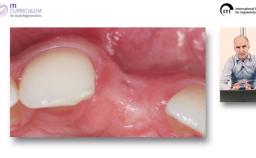

Basierend auf diversen Studien und eigener klinischer Erfahrung stellt Dieter Weingart seine Erkenntnisse und Schlussfolgerungen zum Thema Implantatverlust mit Defektbildung vor. Er illustriert das Thema mit eigenen klinischen Fällen inklusive Langzeit-follow-ups.